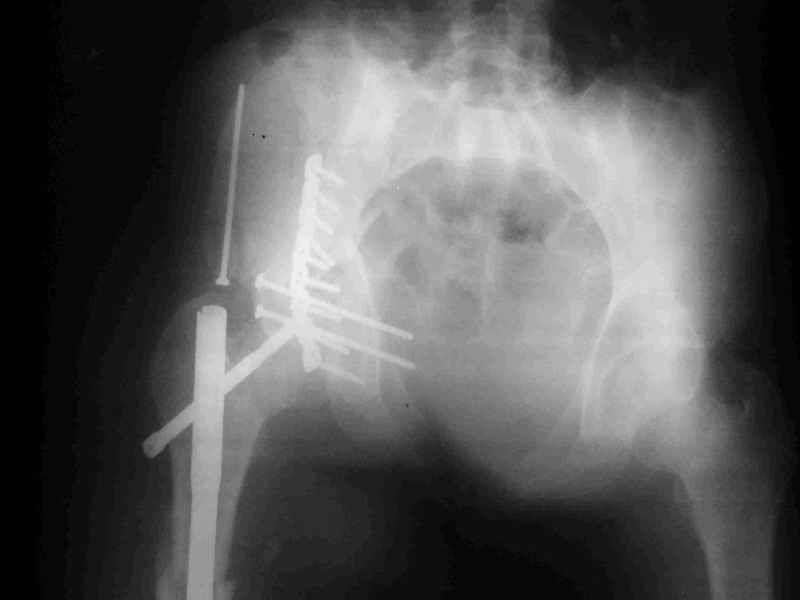

Не дождавшись советов, в понедельник прооперировал больного, заняло времени..., но все сделал в один этап: сначала фиксировал ипсилатеральный перелом бедра и шейки реконструктивным гвоздем Smith&Nephews, потом из расширенного илеофеморального доступа фиксировал перелом крыла подвздошной кости тягловым винтом, нейтрализующей пластиной заднюю колонну, и тягловыми винтами 3,5 мм переднюю колонну.

Несмотря на расширенный доступ, особой кровопотери не было, перелил только одну дозу эр.массы и на утро Нв- 10.5 и как ни странно больной не жалуется на сильные боли и стопа не *висит*, хотя при интраоперационной ревизии седалищного нерва обширная гематома в периневральной оболочке.

К сожалению, набора для ретроградного или антеградного реконструктивного штифтования в операционной нет, поэтому доставка заняла н-ное время. Вопрос, который возник у меня- по поводу оптимальной тактики хирургии: вся фиксация в один этап из расширенного доступа или последовательно сначала бедро и позже реконструкция впадины, комбинированный доступ к впадине отдельно к передней и задней колоннам или из расширенного илеофеморального одного доступа. Все-таки решил остановиться на одноэтапном подходе и спустя 5 дней (как раз и наборы привезли) из расширенного илеофеморального доступа сначала фиксировал реконструктивным штифтом Smith&Nephews бедро и

шейку (благо перелом шейки 2 типа -относительно стабильный) затем фрагмент крыла подвздошной кости Lag screw, далее пластина на заднюю колонну и винты в переднюю колонну.(с размерами и направлением винтов ошибка вышла:-((, но интраоперационно у меня была полная уверенность , что винты *ушли* в лонную кость).

Еще раз спасибо за комментарии и готовность помочь с имплантами. Постоп картинки в приложении,